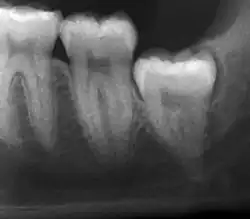

Impacted wisdom teeth are classified by their direction of impaction, their depth compared to the biting surface of adjacent teeth and the amount of the tooth's crown that extends through gum tissue or bone. Impacted wisdom teeth can also be classified by the presence or absence of symptoms and disease. Screening for the presence of wisdom teeth often begins in late adolescence when a partially developed tooth may become impacted. Screening commonly includes a clinical examination as well as x-rays such as panoramic radiographs.

If the tooth cannot be assessed with clinical exam alone, the diagnosis is made using either a panoramic radiograph or cone-beam CT. Where unerupted wisdom teeth still have eruption potential several predictors are used to determine the chance of the teeth becoming impacted. The ratio of space between the tooth crown length and the amount of space available, the angle of the teeth compared to the other teeth are the two most commonly used predictors, with the space ratio being the most accurate. Despite the capacity for movement into early adulthood, the likelihood that the tooth will become impacted can be predicted when the ratio of space available to the length of the crown of the tooth is under 1.[5]: 141